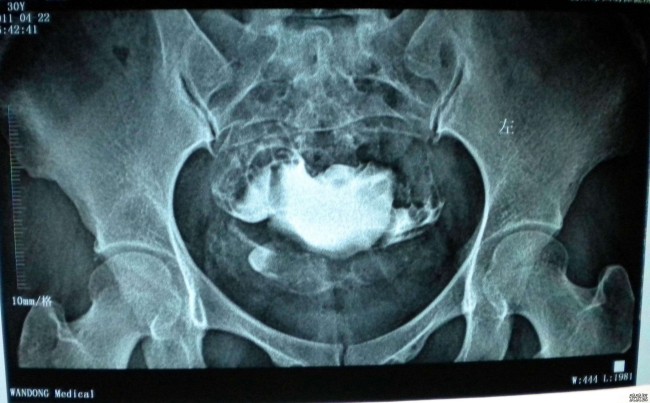

子宫输卵管造影,指的是通过导管向子宫腔及输卵管注入造影剂,在X线下透视及摄片,根据造影剂在输卵管及盆腔内的显影情况了解输卵管是否通畅、阻塞的部位及子宫腔的形态。

子宫输卵管造影是诊断不孕症的常用检查方法之一。和B超、CT及MRI等检查相比,子宫输卵管造影不仅可以清晰显示出的输卵管和子宫的情况,还具备简便易行、费用低的优点。需要注意的是,碘过敏、患有急性生殖器炎症、妊娠期或月经期的女性不能进行子宫输卵管造影检查。